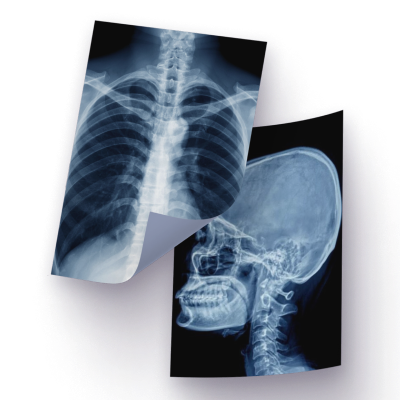

Рентген в Клинике Екатерининская Сочи

Мы проводим цифровую рентгенографию для взрослых и детей с любого возраста — с индивидуальными настройками для высокой точности диагностики и более низкой лучевой нагрузки.

Рентгенография — это метод диагностики, в основе которого — «просвечивание» организма рентгеновскими лучами. Структуры разной плотности пропускают их по-разному. Это и показывают снимки после рентгена. Чем плотнее ткань, тем светлее её визуализация. Поэтому на тёмном фоне снимка так хорошо видны кости.

Хорошая визуализация костной ткани делает рентген диагностическим методом №1 при переломах и других травмах опорно-двигательного аппарата. В то же время на рентгене врач может увидеть уплотнения, скопления жидкости, присутствие газа в полостях и органах.

Поэтому рентген также позволяет диагностировать новообразования, участки воспаления при пневмонии, кишечную непроходимость и многие другие патологии.